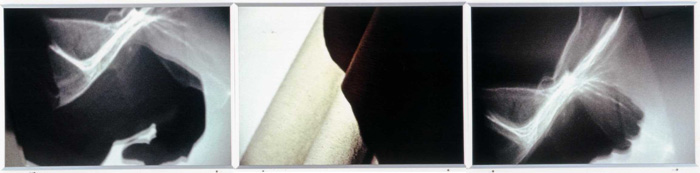

o.T. 3-teilige Fotoarbeit, 210x50cm, 2002